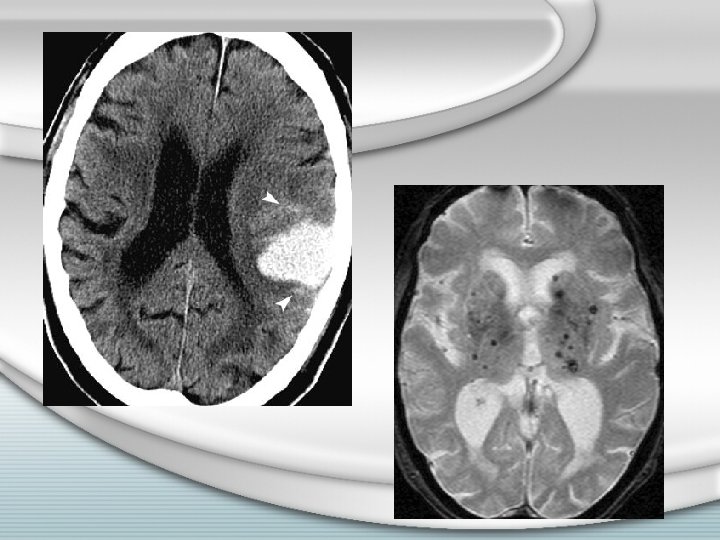

Imagerie • En urgence : – SCANNER cérébral – Sans injection • Collection intraparenchymateuse hyperdense • Effet de masse +/- œdème • Parfois : – Image surajoutée – Hydrocéphalie obstructive

Imagerie • En urgence, après le scanner, parfois : – Angiographie cérébrale – Angioscanner ou angio. IRM – IRM • Quand ? – – – Sujet jeune Pas d’HTA connue Topographie de l’hématome atypique Hétérogénéité de l’hyperdensité au scanner Hémorragie méningée associée / hématome en rapport avec le polygone de Willis / vallée sylvienne – Imagerie à refaire en différé parfois

• Selon l’hématome : – Hématome lobaire – Hématome cérébelleux : si unilatéral, hémisphérique, et mal toléré – Hématome lenticulaire / thalamique : indications limitées aux aggravations secondaires chez des sujets jeunes

• Contre-indications chirurgicales : – Sujet âgé – Coma profond – Troubles de l’hémostase non corrigés – Suspicion d’angiopathie amyloïde – Hématome cérébelleux bilatéral – Hématome du tronc cérébral – Hématome lenticulaire + hypothalamus